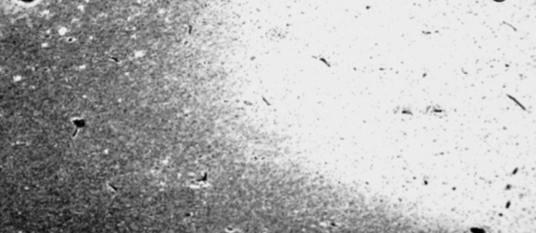

What is going on in this luxol fast blue stained image?

What is going on at a cellular level in these MS plaques?

How are axons affected in MS plaques?